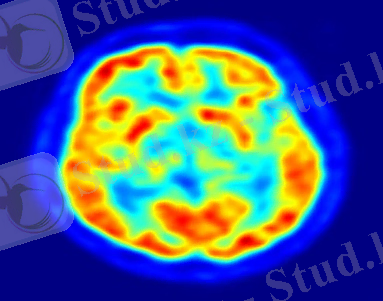

Орталық нерв жүйесінің негізгі бөлігі - ми. Ол ми сауытында орналасқан. Ересек адамда мидың салмағы 1400-1450 грамм құрайды. Мидан 12 жұп жүйкелер тарап, миды көптеген ішкі мүшелермен, беттің, мойынның еттерімен, тілмен, көзбен байланыстырады және сезім мүшелерінен келген ақпаратты миға жеткізеді. Бұларға I - иіс, II - көру, III - көз қимылдатқыш, IV - шығыршық, V - үшкіл, VI - бұру, VII - бет, VIII - дыбыс, IX - тіл-жұтқыншақ, X - кезеген, XI - қосымша, XII - тіласты жүйкелері жатады. Ми артқы ми, (сопақша ми мен варолий көпірі), мишық, ортаңғы ми, аралық ми жєне екі ми сыңарларынан тұрады.

Ми әрқайсысы жарты шарға ұқсас қос ми сыңарынан, мишық пен ми бағанынан тұрады.